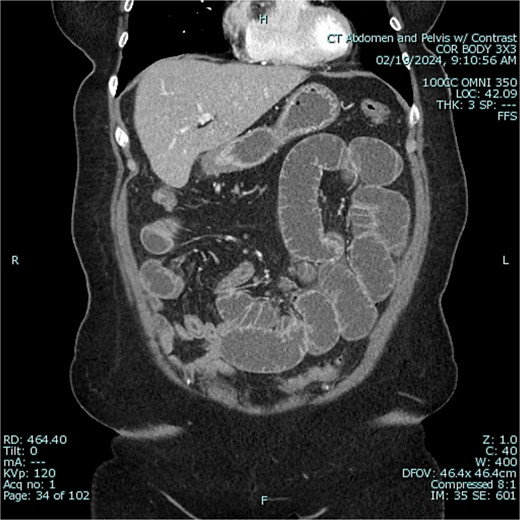

The patient was admitted to the hospital for conservative management of suspected adhesive SBO. She was treated with intravenous fluid hydration and nasogastric tube decompression. On hospital days 2–4, she began to feel better and pass flatus. Gastrografin challenge revealed passage of contrast through the small intestine and into the colon (Figs 3 and 4). On hospital day 5, however, she had cessation of bowel function with worsening abdominal pain, tachycardia, and leukocytosis (WBC 16 K/μl).

Gastrografin challenge reveals passage of contrast through the small intestine and into the colon on sequential imaging [300 × 361 mm (72 × 72 DPI)].